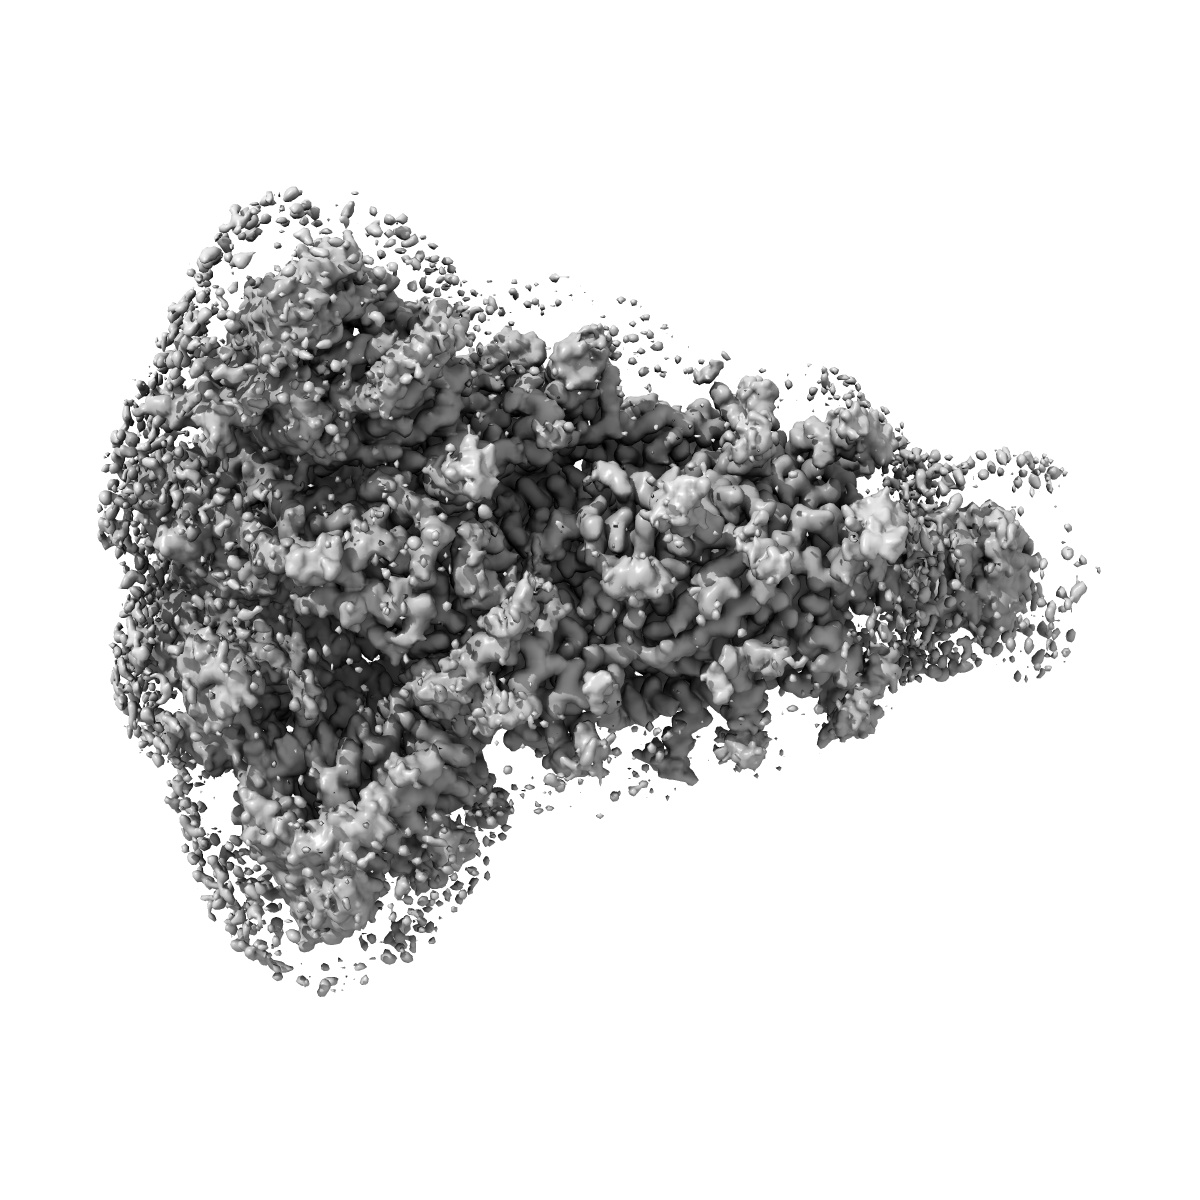

EMD-26021

Structural and functional impact by SARS-CoV-2 Omicron spike mutations

Single-particle3.1 Å

Sample: Closed state of pre-fusion SARS-CoV-2 Omicron variant spike protein